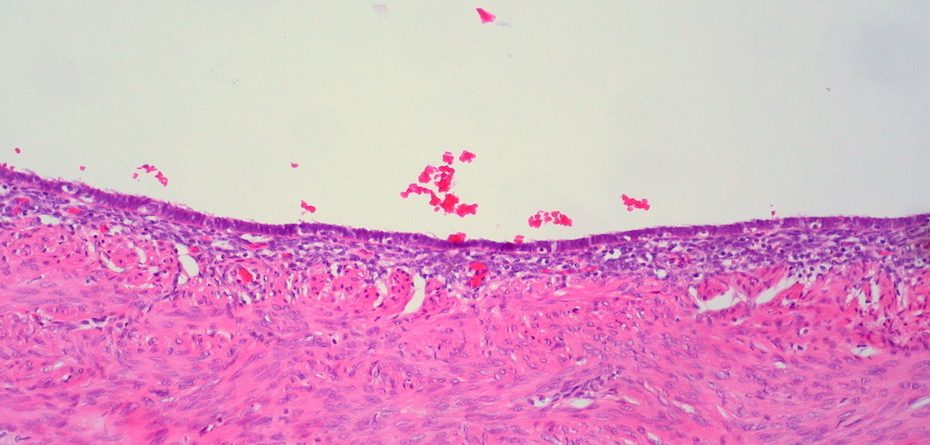

More than 176 million women worldwide, regardless of ethnicity, race or social class have Endometriosis. Yet, very little is known. This is a chronic, painful and debilitating disease, in which the tissue that usually makes up the lining of the uterus is found on other organs in and around the body. Although most symptoms are indicative of a “normal” menstrual cycle, there are some symptoms that are synonymous only to endometriosis, and may include; pain with intercourse, painful bowel movements, excessive bleeding and infertility. As to what causes this condition, there is no definitive answer.